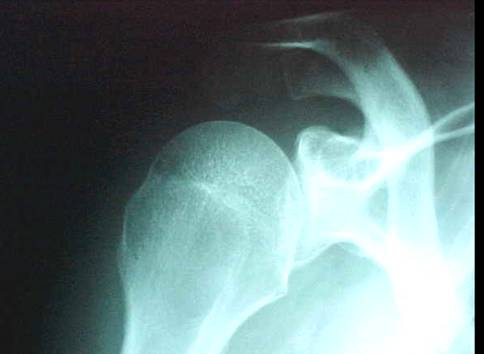

RX No. 5: Axilar

5 – Axilar